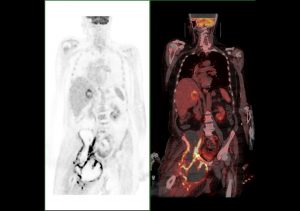

Masse collectée en fosse iliaque droite, développée en regard du muscle iliaque droit, s’étendant à la région des adducteurs et du triangle fémoral homolatéraux, lobulée, de métabolisme hétérogène.

Je suis bien intrigué par cette masse… Ça ne fait pas trop métastase tissulaire, trop gros, volumineux paquet à développement régional, densité homogène à prédominance hydrique, métabolisme périphérique… L’os n’a pas l’air envahi

Seconde maladie qui n’a rien à voir avec le néo pulmonaire?

Cette présentation était intéressante car l’extension hépatique et ganglionnaire rétro-cave peut également se voir dans les tumeurs desmoplastiques. Il était donc difficile de faire la part des choses entre une extension secondaire d’origine pulmonaire ou tumorale desmoplastique.